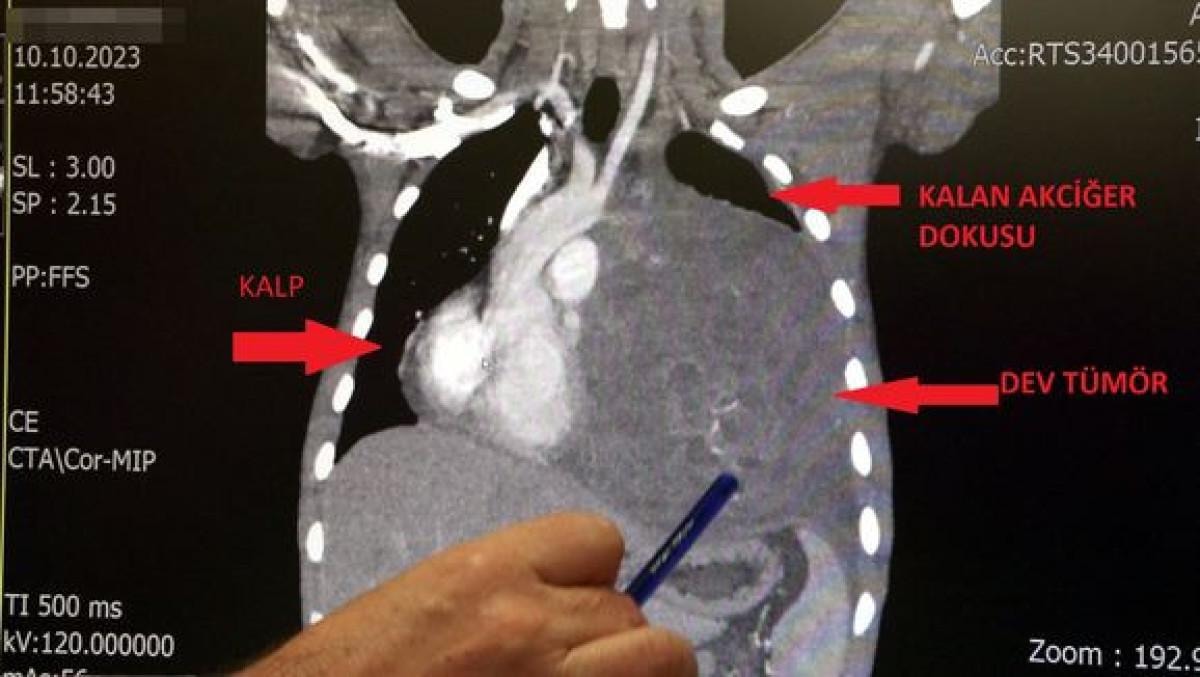

Sol akciğerinin yüzde seksenini kağıt gibi ezen, kalbini göğüs duvarında 12 santim sağa kaydıran ve hem kalbe hem beyne giden ana damarlara baskı yapan 6.5 kilo ağırlığındaki dev tümör, doktorların birlikte girdiği operasyonla başarılı şekilde çıkarıldı.

Operasyon sırasında Aktaş'ın kalbi normal yerine çekildi, sol akciğerin üst lobu alındı, ezilen alt lobu ise anestezi ekipleri tarafından pozitif basınçla yeniden şişirildi.

Göğüs boşluğunda kemik kafesi içinde olduğu için, itebileceği iki organ var; biri kalp, diğeri de akciğerler. Soldan sağa doğru büyüdüğü için kalbi tamamen göğüs boşluğunun sağ tarafına itmiş ve kalbe giren ve kalpten çıkan bütün büyük damarları da yer değiştirmenin etkisiyle bükülmüş durumdaydı. Bu nedenle vücuduna yeterince kan gitmiyordu. Ağustos ayının başında portakal büyüklüğündeyken kitle Eylül sonuna irice bir kavun, Ekim ayına geldiğimizde ise bir karpuz büyüklüğüne ulaştığı için, kitlenin büyüme hızı bizi acilen ameliyat yapmaya yöneltti. Yaklaşık 8-10 kat hacimsel olarak artmıştı. Sol akciğer tamamen ezilmiş ve kağıt haldeydi, alt lobu anestezi ekibimiz yüksek basınç uygulayarak tekrar şişirdi. Çok fazla vaktimiz yoktu, kitle basısından dolayı yaşamla bağdaşmayacağından dolayı hızlı hareket etmek zorundaydık. Bize geldikten üç gün sonra hemen ameliyata aldık çünkü tümörden ziyade onun yaptığı baskıdan kaynaklı hayati riski vardı.

"Kalbi tekrar eski pozisyonuna getirdik"

Bu hastada yaklaşık 12-13 santimlik kalbin alt ucununu yer değiştirmesi ve kalbe giren çıkan bütün damarlar bükülüp kan akımı bozulmuştu. Kalp Damar Cerrahisi ekibi de bizimle beraber ameliyata girdi. Sol akciğerin üst lobu artık geri dönüşümsüz olarak ezildiği için çıkarmak zorunda kaldık. Kalbi tekrar eski pozisyonuna getirdik. Ameliyat sonrası çok çabuk toparladı. Bundan sonra onkolog arkadaşlarımız hastamızın yaşamına çok olumlu dokunuşlar yapacak. İmmatür teratom genelde embriyojenik çağda gelişim gösteren germ hücrelerinin farklılaşmasıyla büyür. Vücudun herhangi bir yerinde gelişebilir ve içinde saç, diş, kemik artıkları, jölemsi kıvamda maddeler bulundurabilen bir tümör çeşididir. Kombine tedavilerde çok iyi sonuçlar alınıyor. Bu çocuğumuzu ileride güzel bir hayat bekliyor.